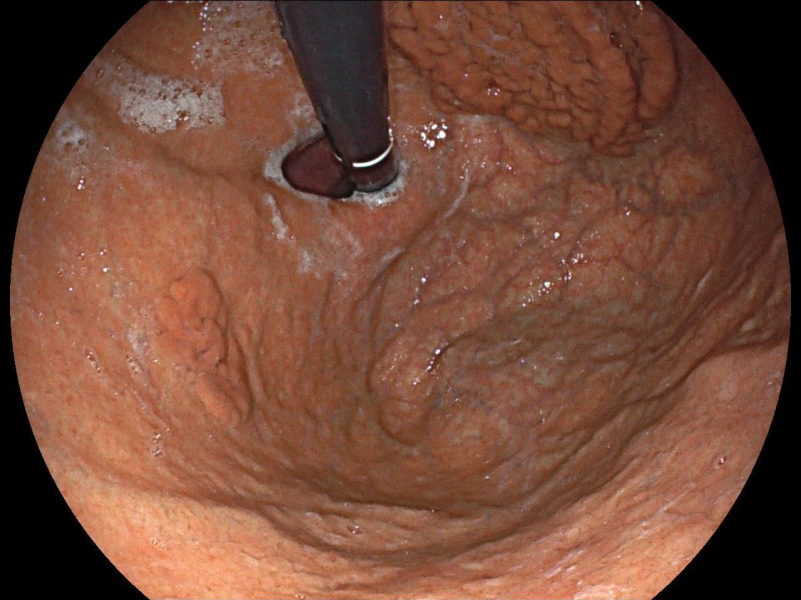

[1º CLASSIFICADO] From the ileum to the stoma - Silent multiple lymphomatous polyposis in mantle cell lymphoma

Fotografia